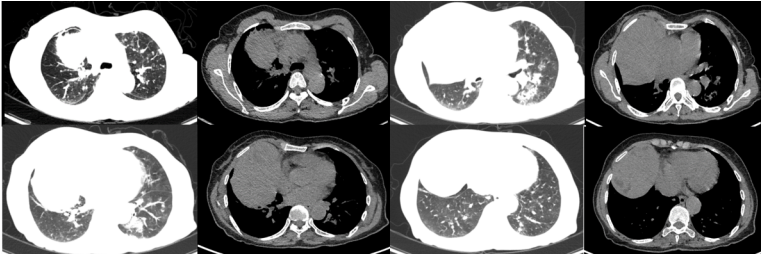

2021年10月9日胸部CT:两肺渗出,类似间质性改变(图4)

图片

图4  患者胸部CT(2021-09-14)

11月3日复查胸部CT见病变较前明显改善(图5)。11月4日,患者改为鼻导管吸氧。

图5  患者胸部CT对比

回顾患者病程,2021年3月12日我院PET-CT结果显示肺部已有少许渗出影(图6),至10月患者病情加重,因此考虑皮肌炎可能与胸腺瘤有一定的相关性。

图6  患者PET-CT表现